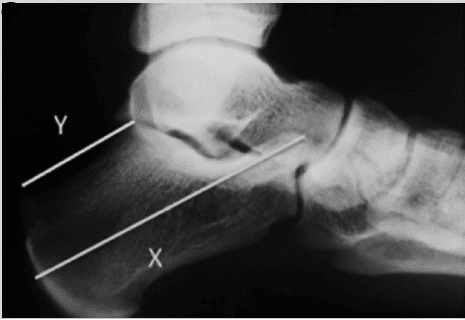

A deformidade de Haglund é um aumento ósseo anormal na região posterossuperior do calcâneo, onde o tendão do calcâneo se insere. Essa protuberância pode ser facilmente visualizada (ver Figura 1) e palpável durante o exame físico.

Radiografias simples e ressonância magnética podem confirmar anormalidades ósseas, mas a correlação com detalhes ultrassonográficos dos tecidos moles corrobora o diagnóstico. Outras causas de dor no calcanhar incluem bursite retrocalcânea/superficial isolada, artropatias sistêmicas e ruptura do tendão calcâneo.